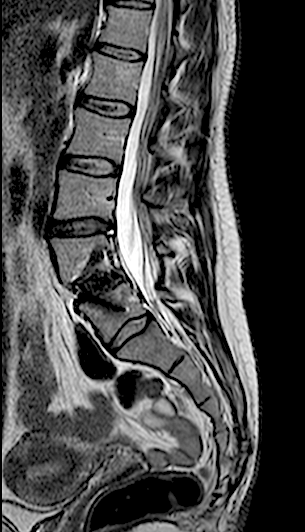

En la RM lumbar de control se apreciaba edema en L5-L6 que se interpretó como secundario a sobrecarga mecánica a dicho nivel. Se decidió una fijación percutánea (MIS) L5-L6.

Tras la fijación percutánea, la paciente seguía presentando lumbalgia mecánica (de menor intensidad). Tras agotar opciones de tratamiento conservador, atribuimos como causa la discopatía incipiente L4-L5 (que había progresado).

Se intervino mediante un abordaje abierto (me parece muy a tener en cuenta que, las reintervenciones de los niveles adyacentes en cirugías percutáneas (MIS) deben realizarse en abierto para conectar el sistema!!) sin complicaciones, con buen resultado radiológico y clínico inicial. La paciente fue remitida a Rehabilitación.

RX 6 meses